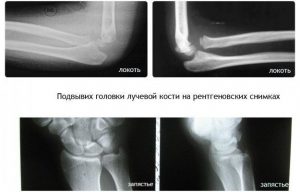

Головка лучевой кости у ребенка

Вывих головки лучевой кости у детей младшего возраста до 3 лет — частая травма. Дети дошкольного возраста также входят в группу риска, но после 6 лет этот диагноз встречается довольно редко. У маленьких детей эта проблема может возникать не раз. Рассмотрим, как распознать травматический диагноз и как лечить патологию. Строение и причины возникновения вывиха В …